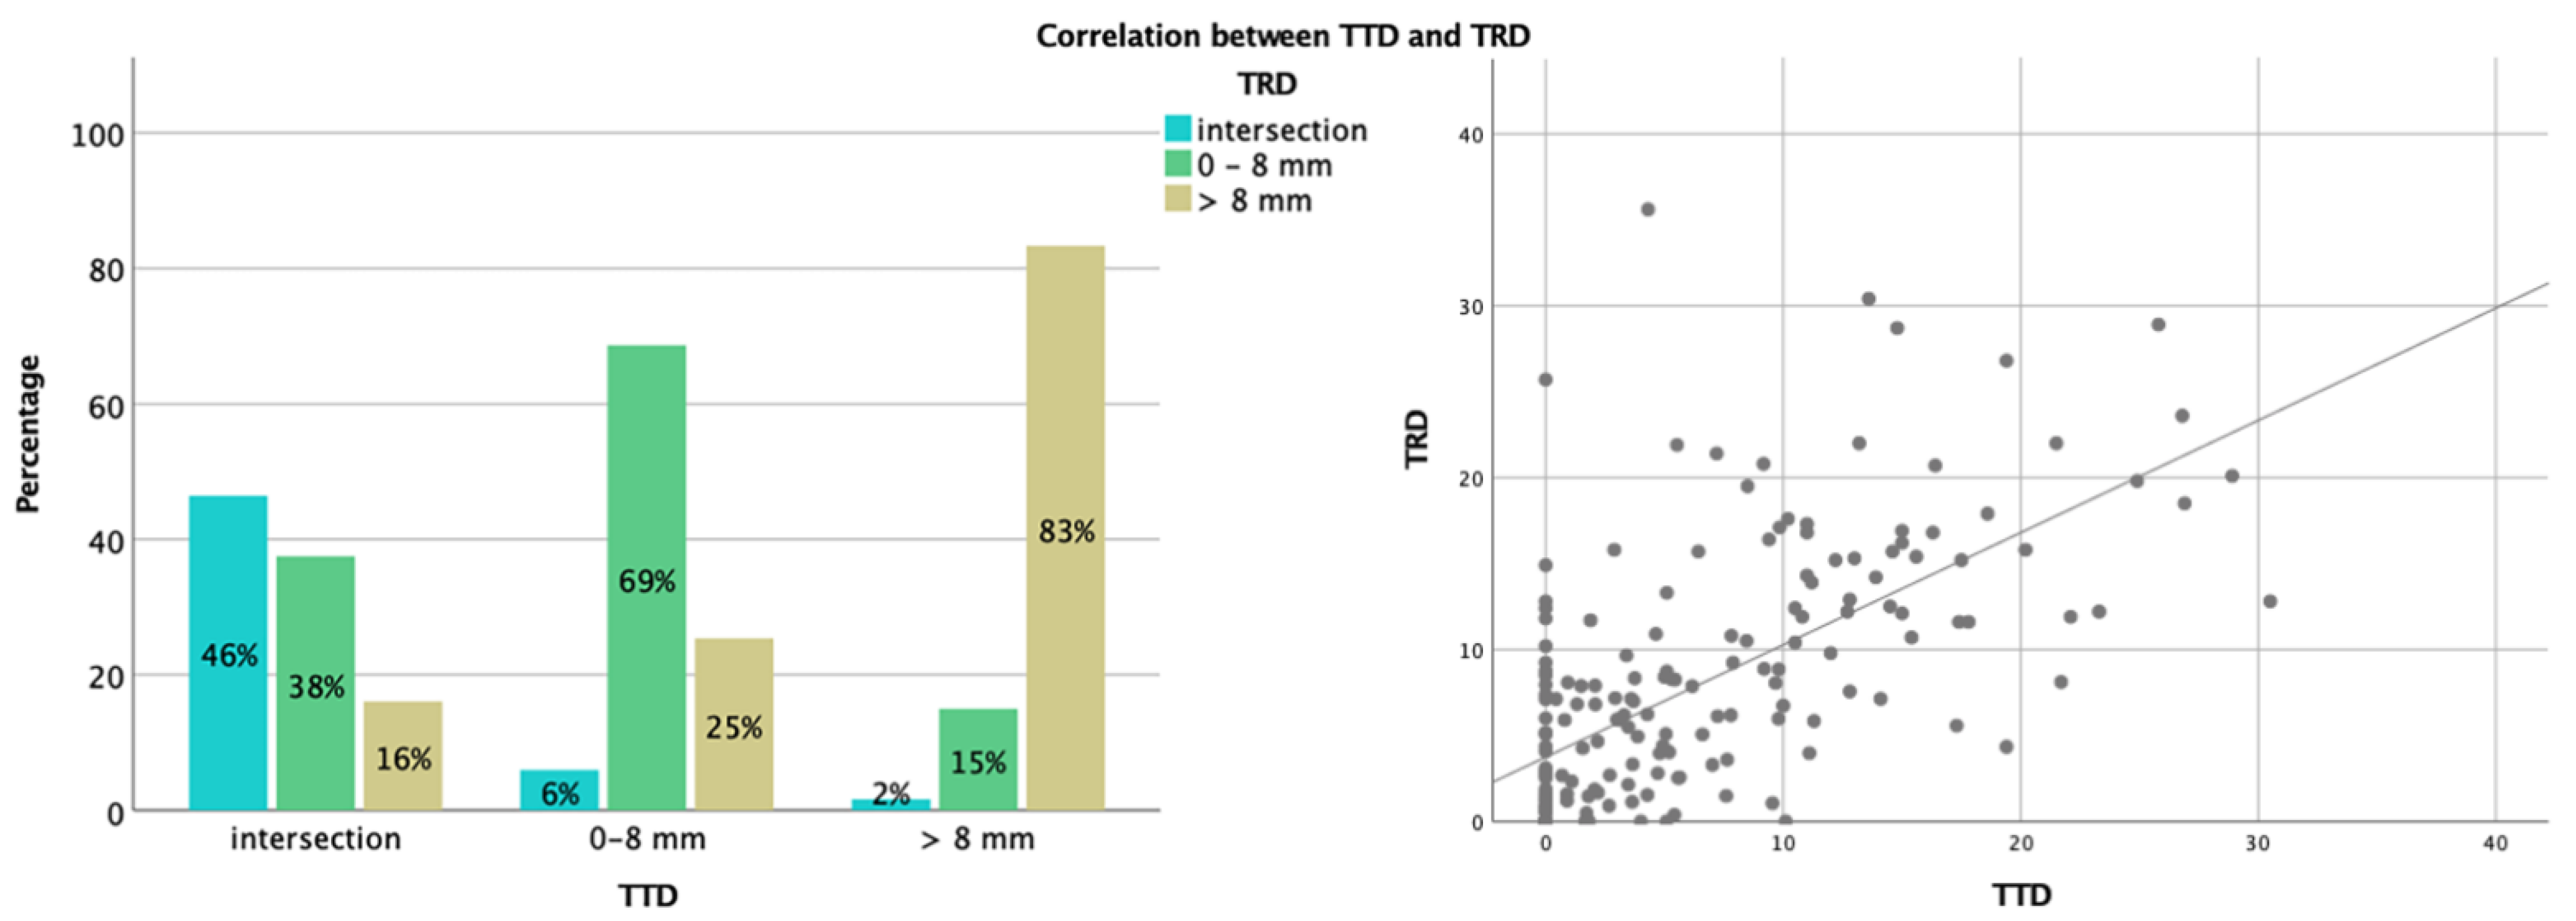

3.2. Analysis of TTD and TRD

3.3. Correlation between TTD, TRD, and Extent of Resection (or Residual Volume)